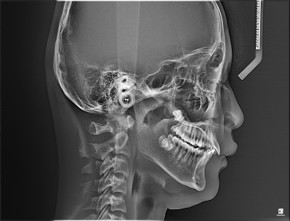

오늘은 심한 무턱 증상으로 윗 치아 쪽이 많이 튀어나와 보이던 성장기 환자분을 소개시켜드리려 합니다.

환자분도 치료 결과에 너무 신기해 하셨지만 무엇보다 어머님께서 너무나 만족하셔서 저희도 뿌듯했던 케이스입니다. |